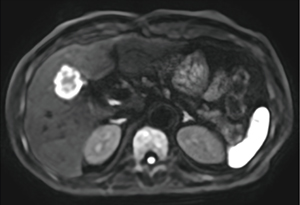

前田医師は、Vantage Centurianで撮像した転移性肝腫瘍の症例(図1)について、「臨床稼働後、最初期に撮像した画像でしたが、DWIで腫瘍が高信号に描出されるだけでなく、腫瘍中心部と辺縁部の信号のコントラストが鮮明に描出されており、Vantage Centurianの分解能の高さを実感しました」と述べる。また、膵臓の膵管内乳頭粘液性腫瘍(IPMN)の症例(図2)でも、PIQEを使用することで分解能が向上し従来画像よりも解像度が向上している。前田医師は、「PIQEの再構成画像では膵囊胞性病変の内部構造が非常にクリアになり、隔壁や充実成分のより詳細な評価が可能になるため、悪性度の評価が容易になります」と評価する。中村准教授はPIQEについて、「Vantage Centurianでは、基本画質の向上とPIQEによる再構成で、コントラストと分解能を両立した画像が得られています。画像の解像度が向上することで、病変の存在や悪性度などを悩まずに確信を持って読影することができます。不明瞭な画像では、ほかのシーケンスやモダリティの画像を確認することになるので、読影時間の短縮にもつながります」と述べる。

図2 IPMN(脂肪抑制T2WI 左:従来型再構成、右:PIQE再構成)